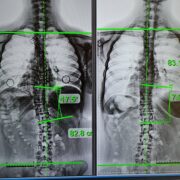

“Doctors will perform a digital rectum examination, where they insert a gloved and lubricated finger into the anus to check for stool buildup. In some cases, a CT scan may be required if impaction happens deep in the colon,” says Dr. Cornejo. “Once fecal impaction is confirmed, they will manually remove the impacted stool using their finger. They may also perform an enema and inject fluid into the rectum to loosen dry stool.”